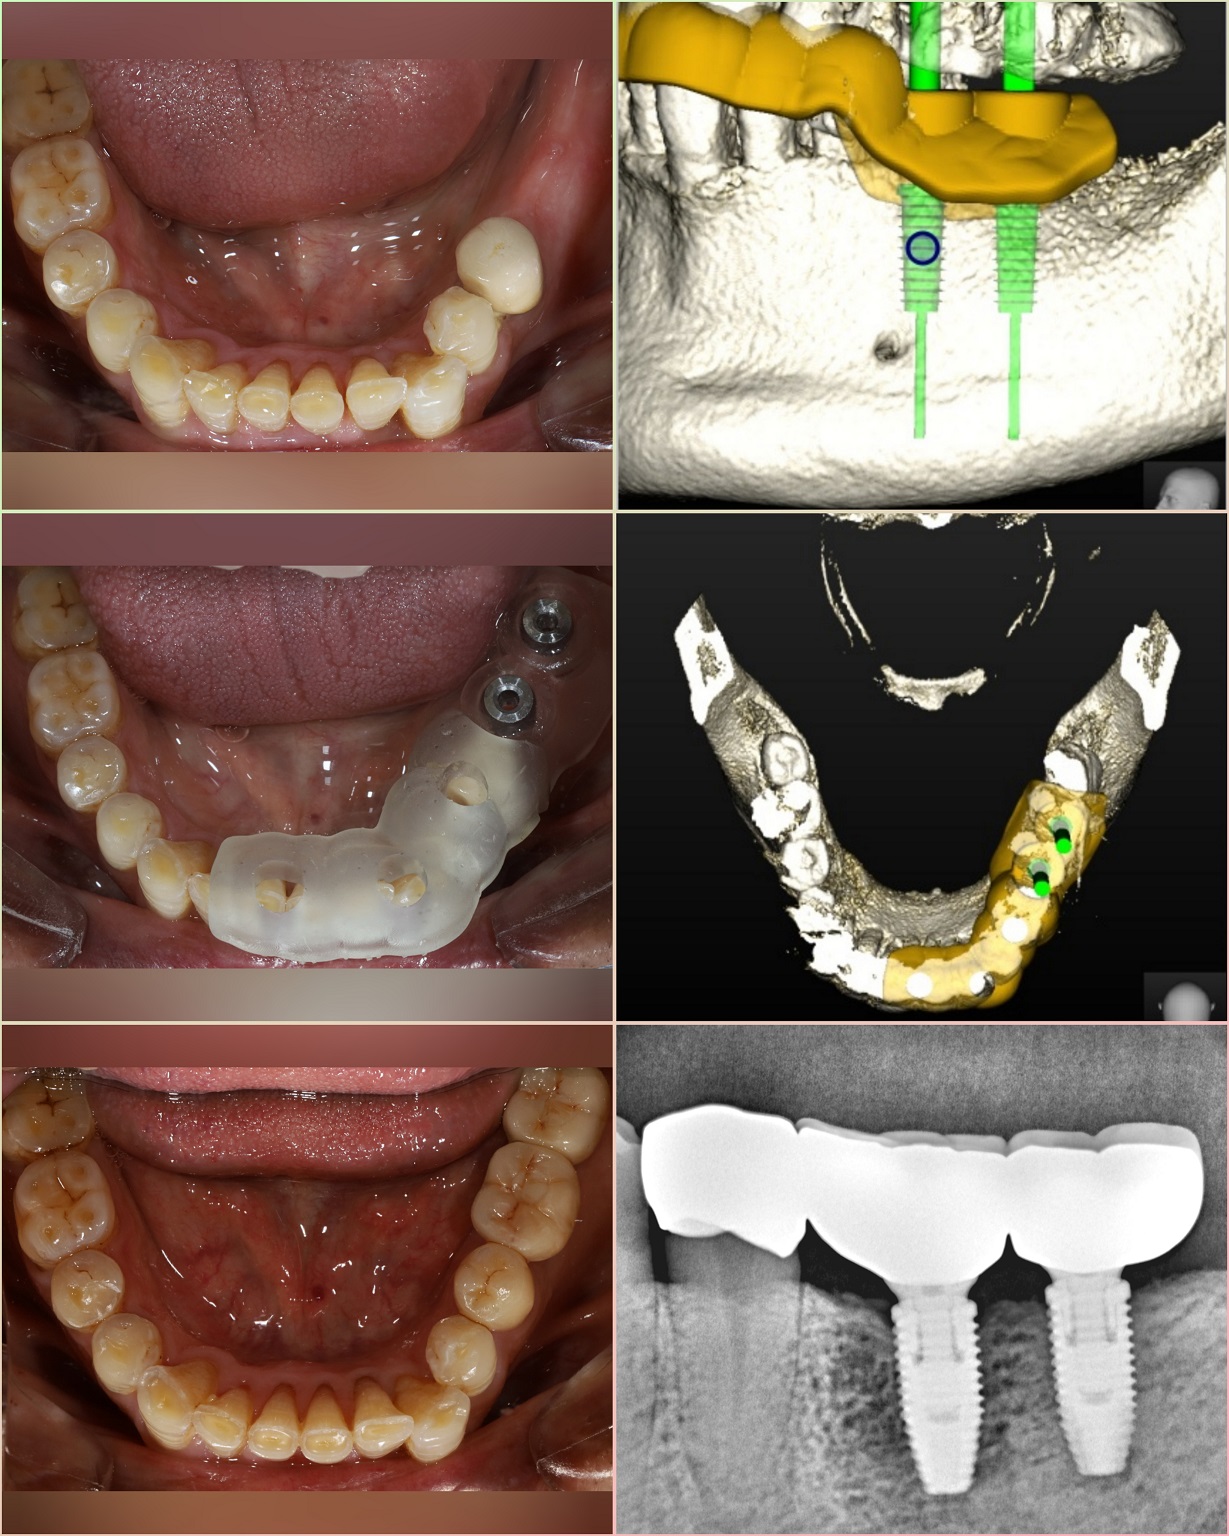

1. We do all implant placement by ‘Robotic Guided Surgery’ for precise, painless, bloodless, stitchless, and fast recovery.

We first create a virtual plan using the implant planning software (Nobel Guide) and also give options of Computer Guided Surgery.

1. No stitches and no gum opening surgery is required.

2. Very fast surgery through the small hole.

3. Less Painful surgery.

4. Very Less post-op discomfort.

5. Flapless procedure – Fast healing.

6. Precise implant placement.

7. No chances of trauma to surrounding vital tissues.

Full mouth Implants – If you are missing all of your teeth, an implant supported fixed denture or bridge is option for you. Replacement of teeth typically needs 6 (All-on-6) to 8 implants to support prosthesis.